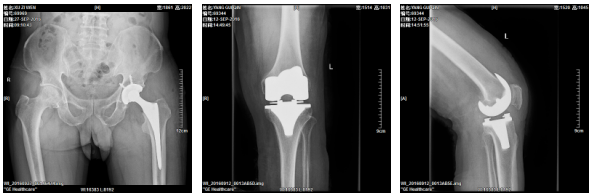

2、髋关节全髋、半髋置换手术、膝关节表面置换手术、关节融合手术。